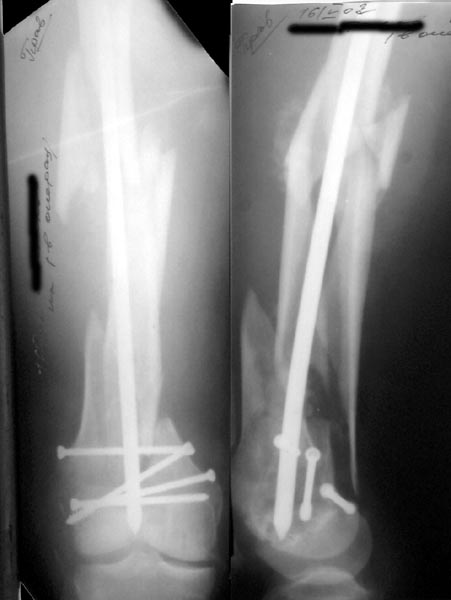

Да, примерно так и сделали. Надо было, пожалуй, кончик гвоздя еще спилить, чтобы отверстие было еще дистальнее. Англоязычные коллеги еще

Мы пошли на операцию с планом попытаться сделать закрытый интрамедулярный, а не получится - сделать аппаратом. Посчитали, что получилось, хотя на еженедельной конференции ожидаются некоторые проблемы с объяснениями ;-)

Насчет стабильности для ранней нагрузки, конечно, сомнительно, но при таком повреждении ранняя нагрузка противопоказана в любом случае. Для ранних движений Должно хватить. Снимки в следующем сообщении.

Since it was done closed the shaft will heal or at worst need an exchange IMN.

Nice job.

IM nails are very forgiving but there are limits. I've seen cases with this postop appearance heal nicely.